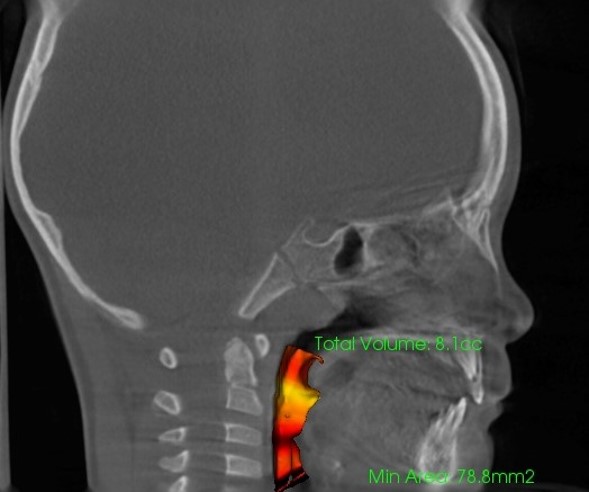

RAMPAによる気道容積の変化イメージ

これらを改善するためには、根本となる骨格への介入が必要不可欠です。

ランパセラピーの特徴は、上顎骨を上前方方向へと3次元的に牽引し、下方に向かっていた中顔面の成長を健全方向へと変化させ、成長を促せることにあります。ここが非常に特殊なアプローチです

この「歪みのない健全な顎骨」への成長誘導によって、気道や鼻腔が拡がり、呼吸器系疾患や耳鼻系疾患に対しての改善が期待できます。